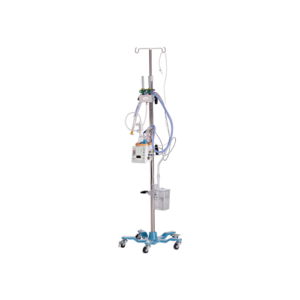

BC 630

Adult Breathing Circuit with Heated Wire for High Flow Oxygen Therapy